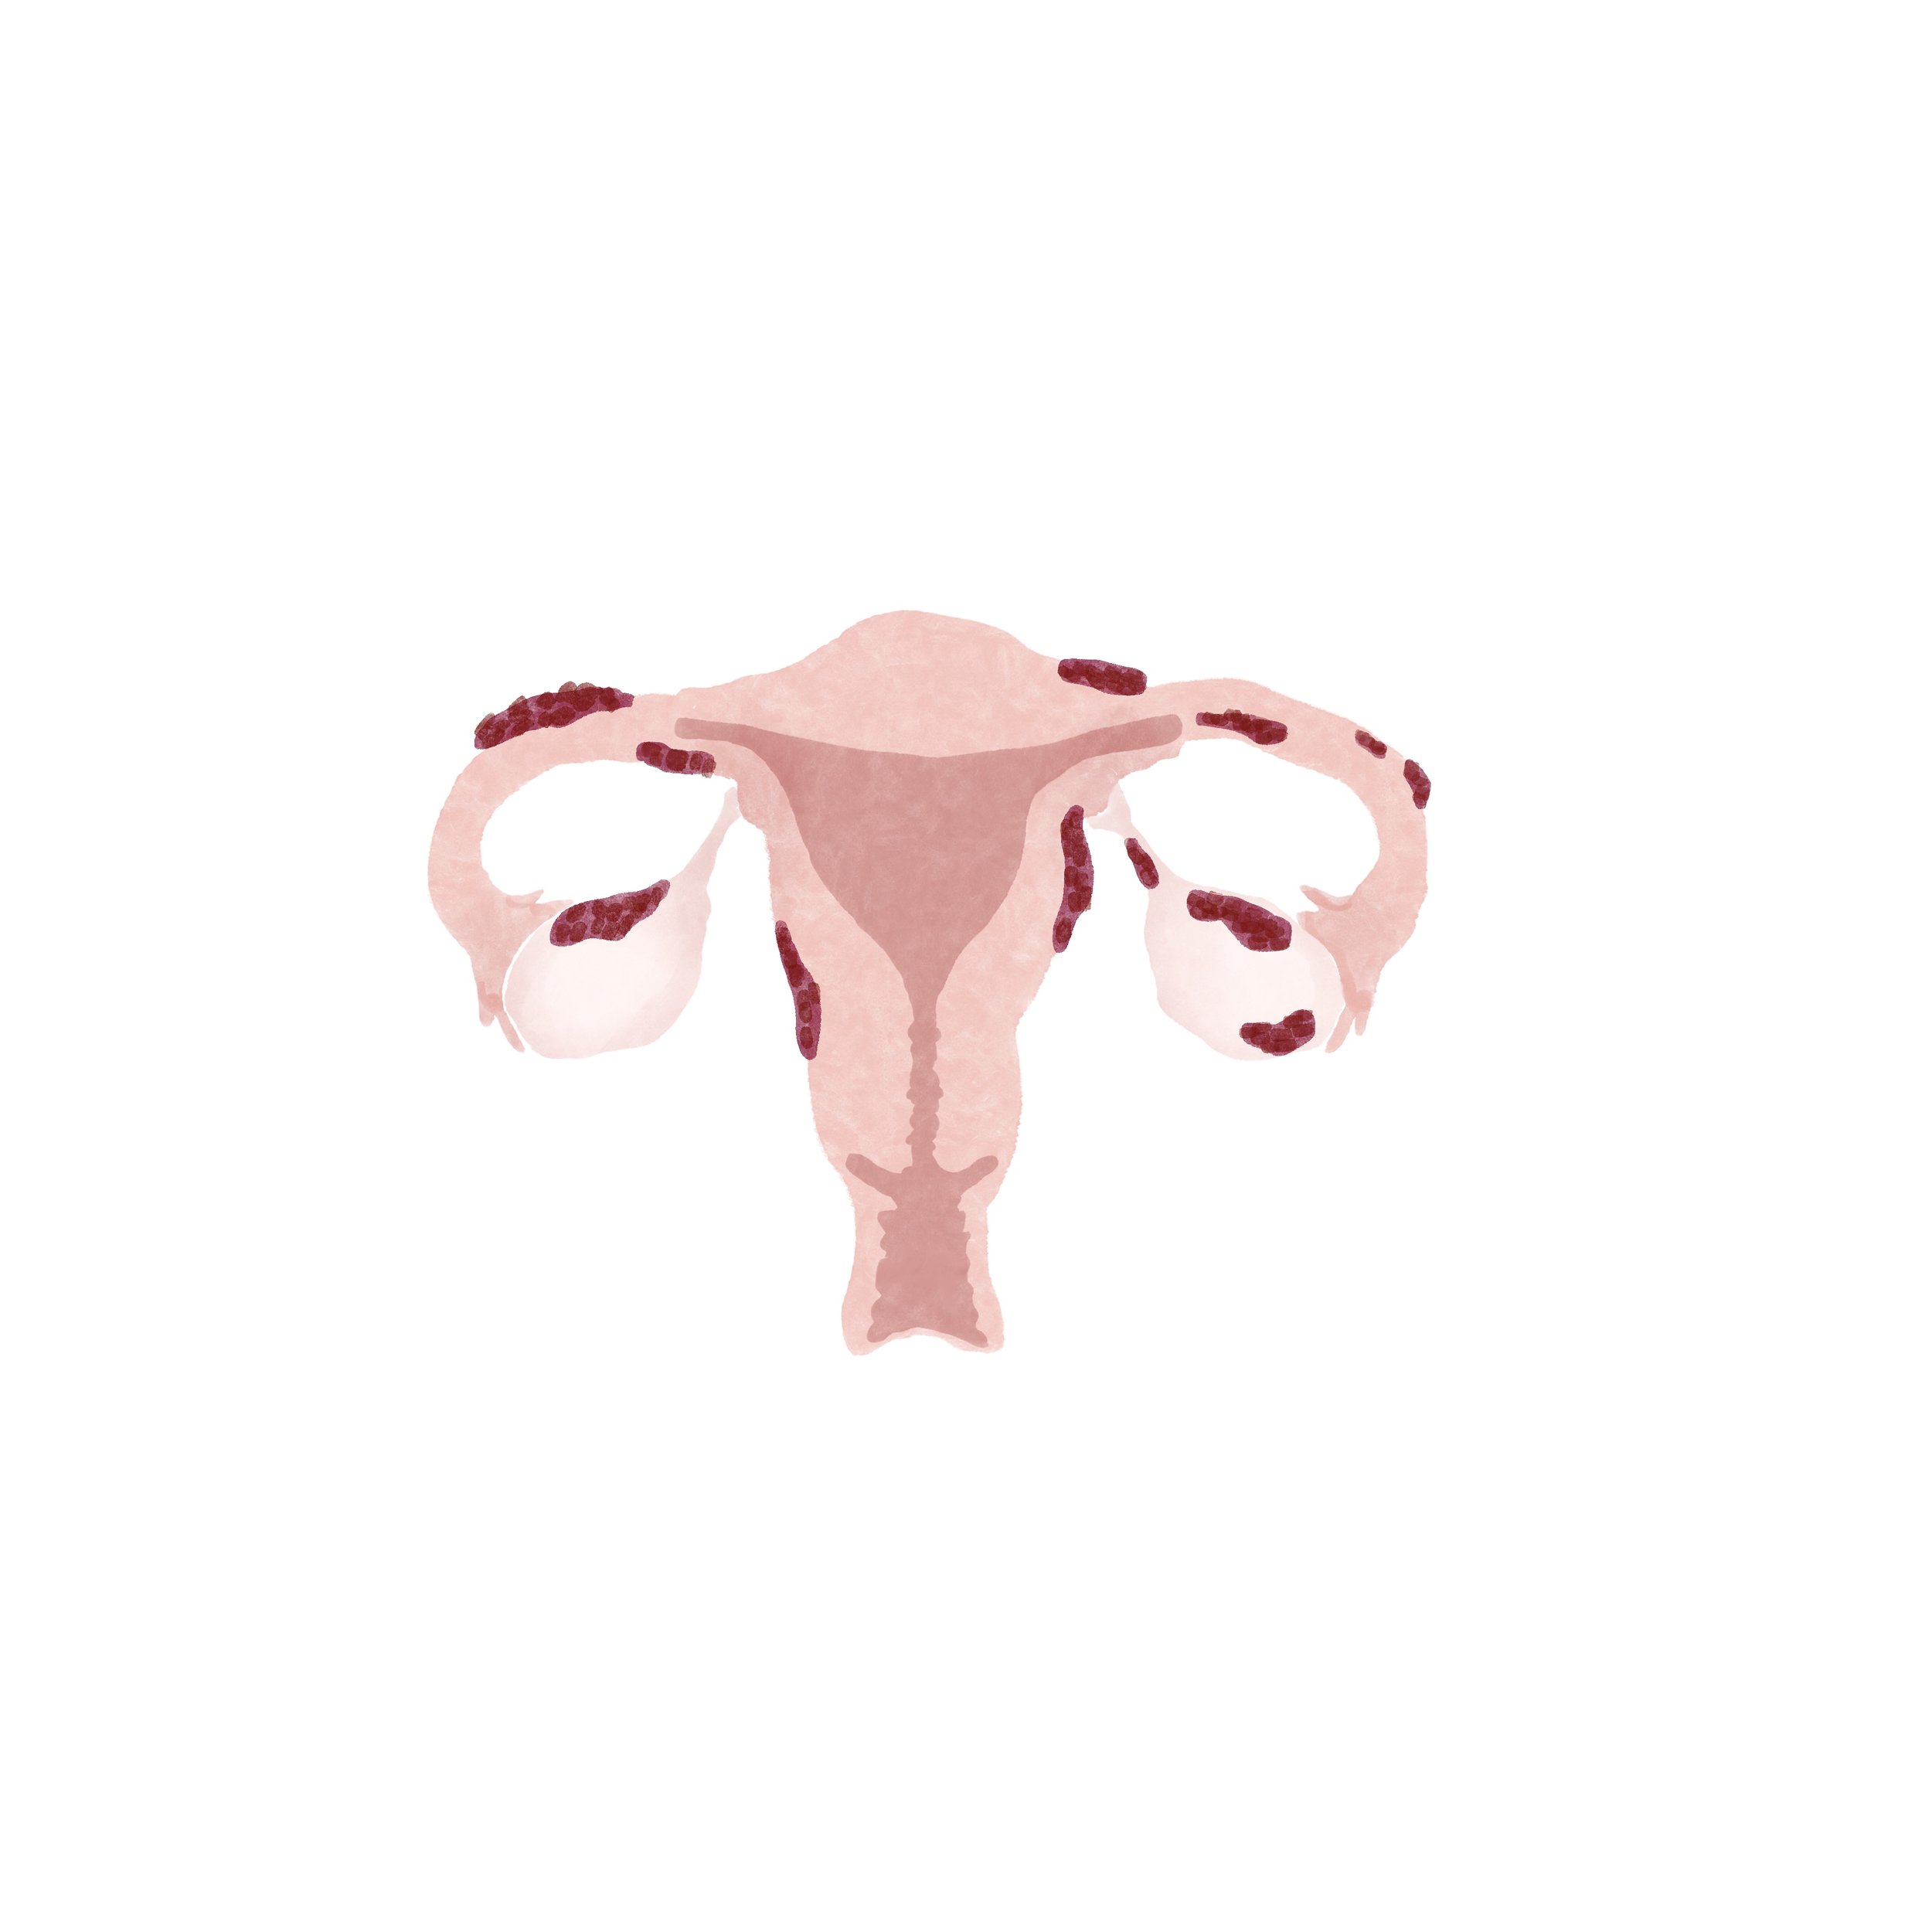

I created watercolor-style digital illustrations for an educational series on reproductive health called “How to Start a Family” for parents.com.

Digital watercolor artwork, 2022.

Endometriosis